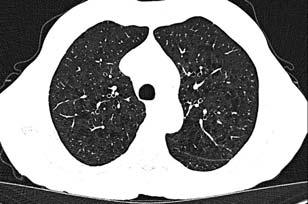

The world’s first singlesource photon-counting CT

siemens-healthineers.ca/naeotom-alpha-prime

Part of the NAEOTOM Alpha class family, NAEOTOM Alpha.Prime is the fastest, highest-resolution single-source CT in our portfolio and is now available in Canada. It expands access to Quantum Technology while preserving the image quality and diagnostic confidence that define the NAEOTOM Alpha class. NAEOTOM Alpha. Prime delivers ultra-high resolution imaging and spectral information in every scan, making photon-counting CT more accessible than ever.

Courtesy of Diagnostikum Graz, Austria The products/features (mentioned herein) are not commercially available in all countries.